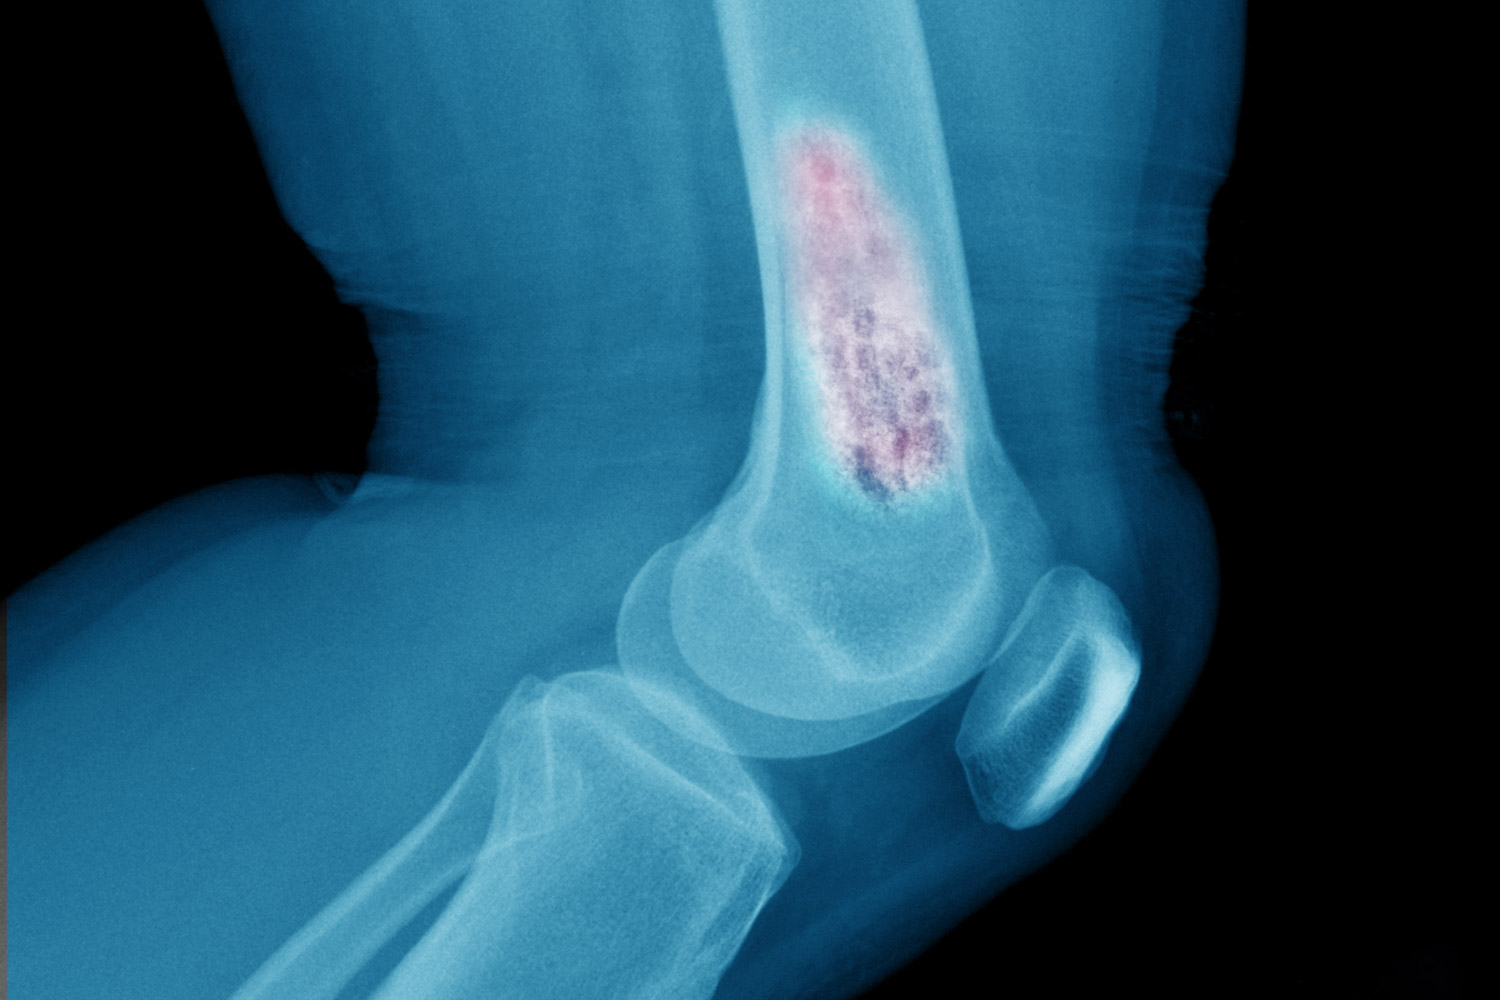

Kemik kanseri nasıl teşhis edilir?

Kemik kanseri teşhisi genellikle fiziksel muayene, görüntüleme testleri (röntgen, MR, BT) ve biyopsi ile konulmaktadır. Bu yöntemler sayesinde doktorlar kanserin varlığını ve yayılımını belirlemeye yardımcı olur.